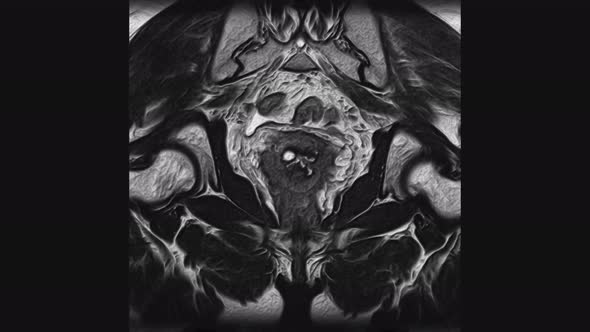

2026's Mind-blowing File Size with 18106mb.